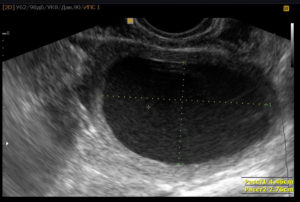

Если у врача имеются подозрения, что после родов в матке остались сгустки крови, он назначает женщине УЗИ. В ходе этой процедуры специалисты внимательно осматривают полость матки, при этом оценивая и общие размеры органа, которые указывают на степень сокращения матки. Чаще при проведении обследования используют трансабдоминальный доступ (датчик помещают на переднюю брюшную стенку).

Отдельно оценивают состояние полости матки. В норме на 2–3-е сутки она должна быть щелевидной или незначительно расширена за счет небольшого количества крови, которая находится в верхней ее части. Смещение кровяных сгустков в нижние отделы происходит на 5–7-е сутки.

Среди возможных отклонений от нормы, указывающих на сгустки в матке после недавних родов:

- чрезмерное расширение полости;

- наличие остатков плацентарной ткани;

- большое скопление крови.